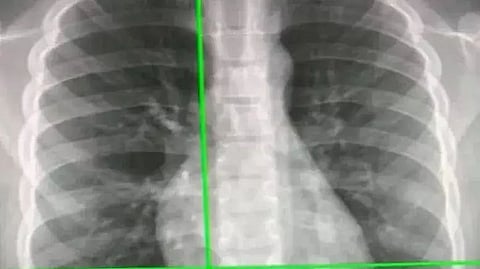

TOKYO: Japanese scientists have developed an advanced artificial intelligence (AI) model that utilises chest radiographs to accurately estimate a patient’s chronological age.

In the case of a disparity, the AI model can signal a correlation with chronic disease. These findings, published in The Lancet Healthy Longevity, mark a leap in medical imaging, paving the way for improved early disease detection and intervention.

The team from Osaka Metropolitan University first constructed a deep learning-based AI model to estimate age from chest radiographs of healthy individuals. They then applied the model to radiographs of patients with known diseases to analyse the relationship between AI-estimated age and each disease. Given that AI trained on a single dataset is prone to overfitting, the researchers collected data from multiple institutions.

For the development, training, internal and external testing of the AI model for age estimation, a total of 67,099 chest radiographs were obtained between 2008 and 2021 from 36,051 healthy individuals who underwent health check-ups at three facilities. The developed model showed a correlation coefficient of 0.95 between the AI-estimated age and chronological age. Generally, a correlation coefficient of 0.9 or higher is considered to be very strong.

To validate the usefulness of AI-estimated age using chest radiographs as a biomarker, an additional 34,197 chest radiographs were compiled from 34,197 patients with known diseases from two other institutions.

The results revealed that the difference between AI-estimated age and the patient’s chronological age was positively correlated with a variety of chronic diseases, such as hypertension, hyperuricemia, and chronic obstructive pulmonary disease. In other words, the higher the AI-estimated age compared to the chronological age, the more likely individuals were to have these diseases. “Chronological age is one of the most critical factors in medicine,” stated graduate student Yasuhito Mitsuyama. “Our results suggest that chest radiography-based apparent age may accurately reflect health conditions beyond chronological age,” Mitsuyama added. (IANS)